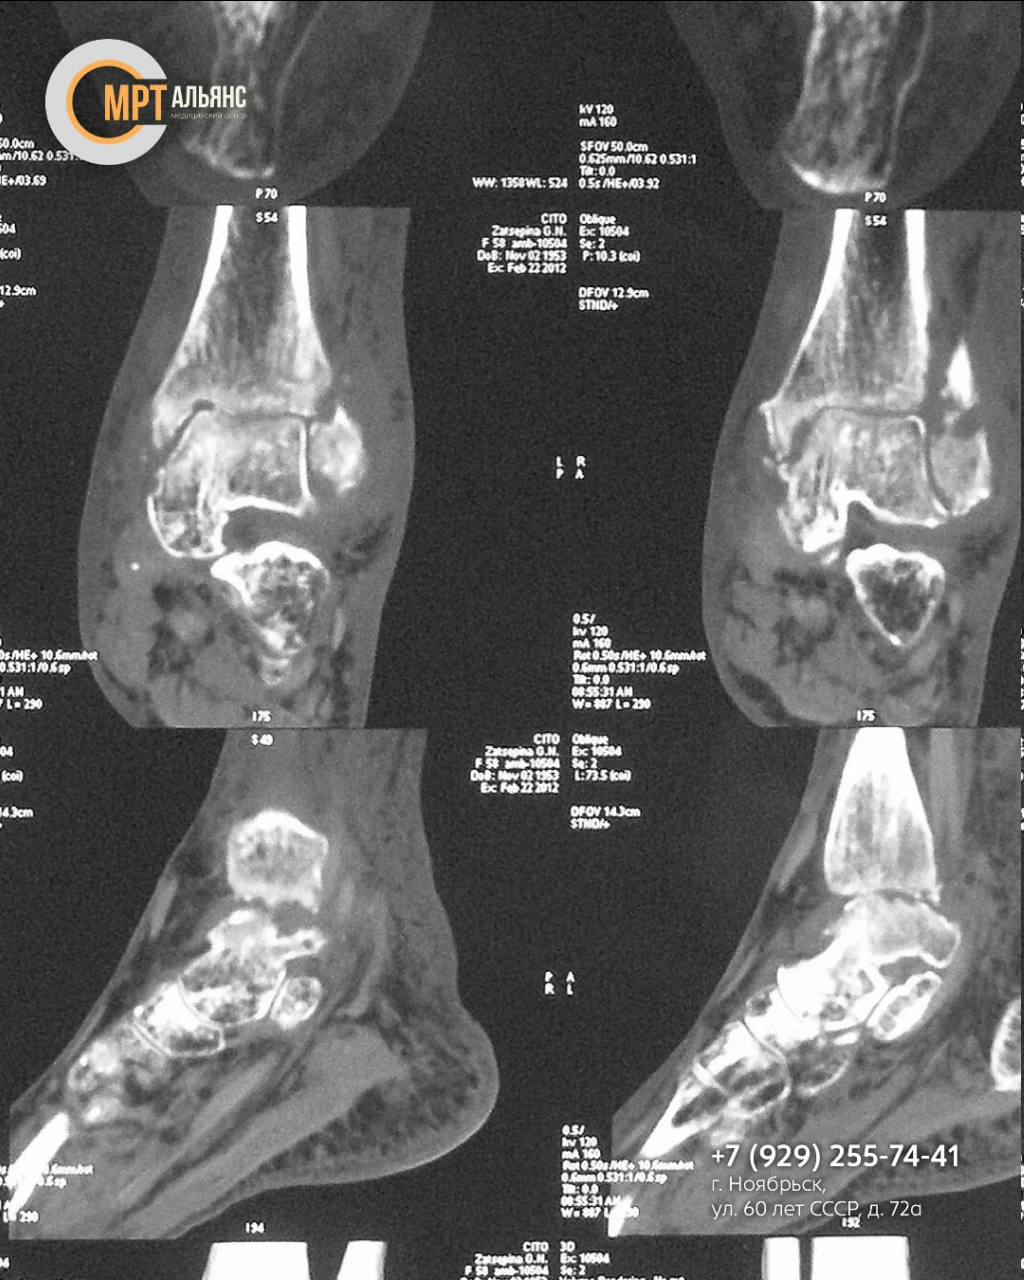

Ваш голеностоп напоминает о себе болью, отеком или дискомфортом? Эти симптомы могут говорить о скрытых проблемах: последствиях недолеченной травмы, воспалении или начале дегенеративных изменений!

Основные показания к МРТ голеностопа:

· Травмы: от растяжений и разрывов связок до переломов и вывихов

· Постоянная боль, отек, ограничение подвижности

· Подозрение на артрит, артроз, тендинит